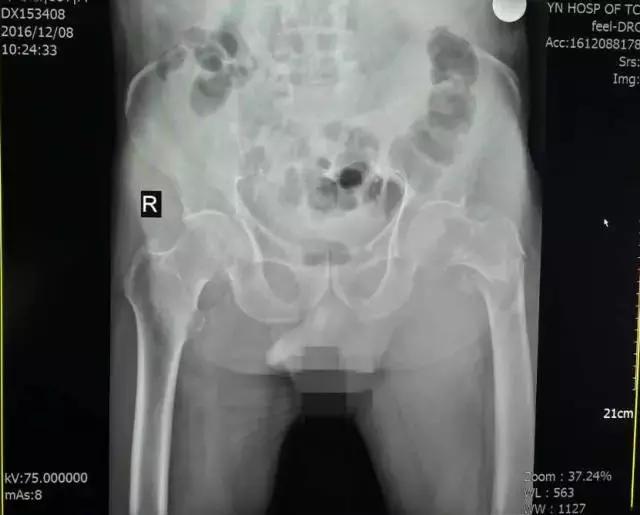

程XX术前X线

程XX术后X线

患者程XX,女,87岁,患者因跌倒致右髋部疼痛,活动受限5天就诊。

入院诊断:1、右侧股骨颈骨折;2、骨质疏松(重度);3、腰椎退行性骨关节病;4、颈椎病;5、双侧膝关节骨关节病;6、左髋关节置换术后;7、白内障;8、消化道溃疡。

诊疗措施:患者因右侧股骨颈骨折伴重度骨质疏松,双膝关节骨性关节病行右侧人工股骨头置换术。术前有重症肺炎,慢性阻塞性肺病,慢性肺源性心脏病等并发症。术中成功置换股骨头,复位后见关节稳定,匹配及活动度良好,术后我科医护人员密切观察患者各项生命体征,积极治疗护理,最终患者恢复了生活自理能力。